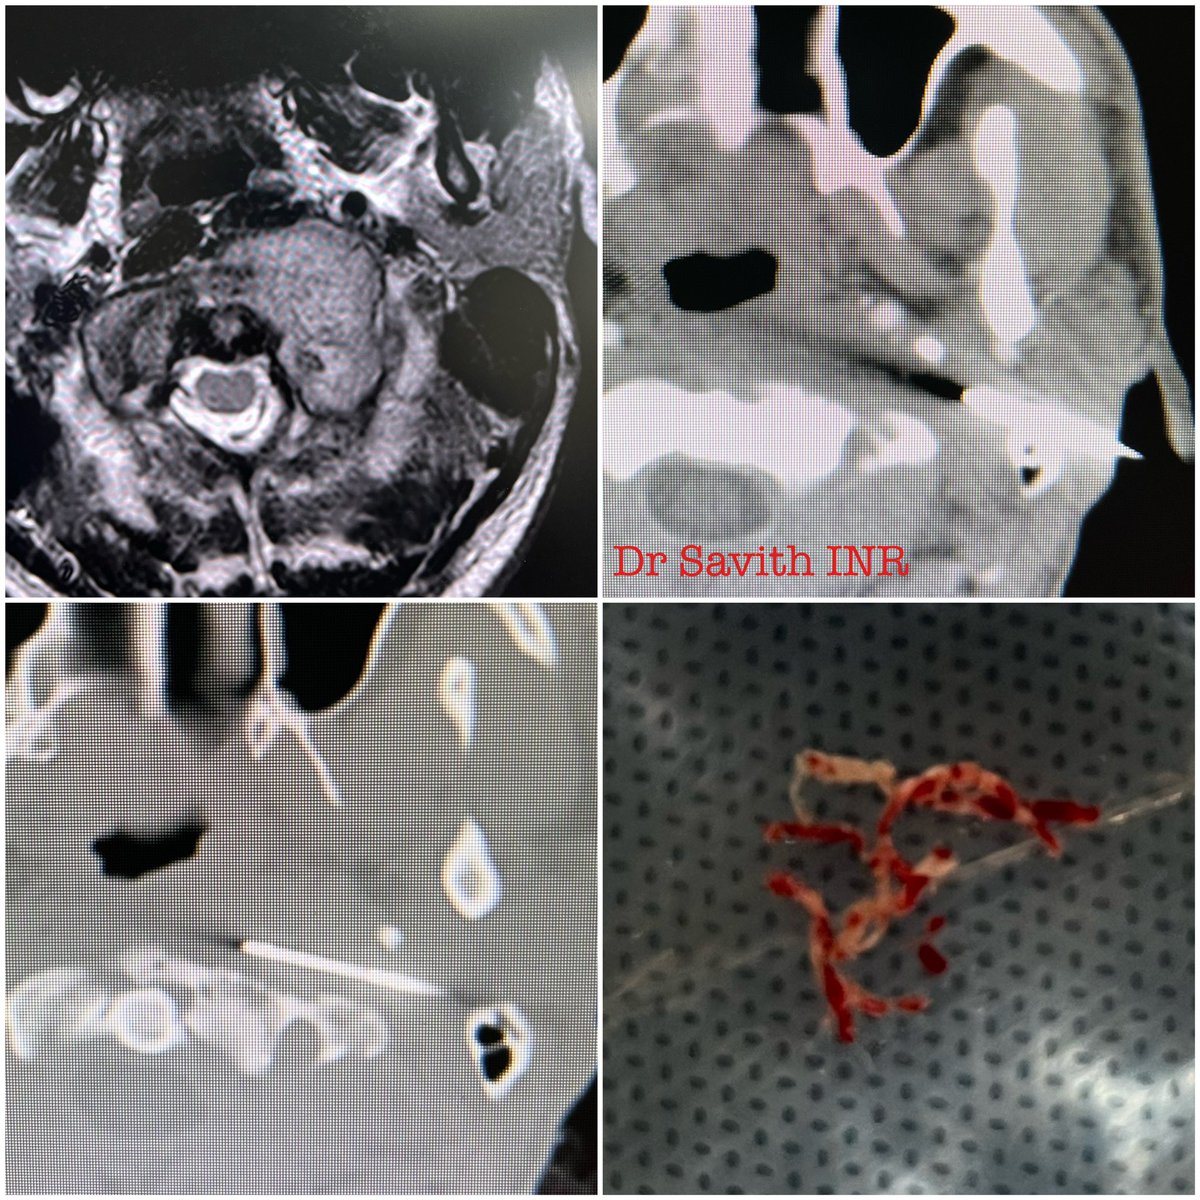

CT guided biopsy of parapharyngeal space lesions(3 cases)

With good anatomical knowledge and careful planning, biopsies of parapharyngeal space lesions can be performed safely.

#interventionalradiology

#minimallyinvasive